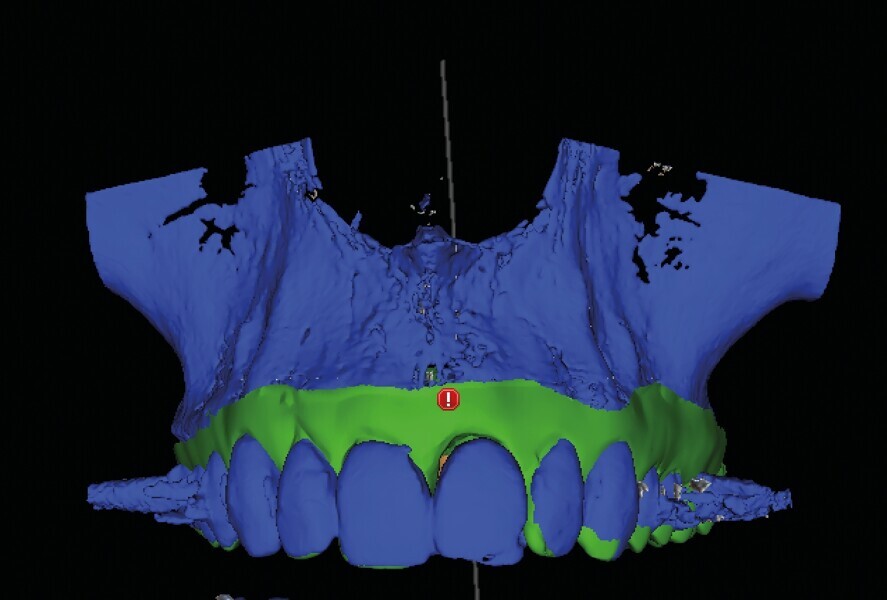

Fig. 2 : Image CBCT en 3D des structures osseuses (b). La lésion périapicale est mise en évidence.

Une fistule avec écoulement purulent est présente en regard de l’apex de la dent. Une tomodensitométrie volumique a faisceau conique (CBCT) est réalisée pour évaluer l’environnement péri-dentaire : l’épaisseur de l’os vestibulaire, la forme de l’alvéole et la position de la racine sur le plan sagittal (Figs. 2–3). Une fracture radiculaire est mise en évidence.

L’endodontiste chez qui la patiente a d’abord été référée a émis un pronostic peu favorable en raison d’une déhiscence osseuse importante en vestibulaire, associée à une fenestration au niveau de l’apex. L’espace inter occlusal est réduit, avec un profond recouvrement incisif. La décision de ne pas conserver cette dent est alors prise. Le choix se porte vers une restauration unitaire implanto-portée.

Dans le cas de la patiente, les tissus mous sont bien positionnés : la dent a subi une égression, mais aucune récession n’est présente. L’os vestibulaire est partiellement absent et classe l’alvéole dans le type II selon Elian et al.2